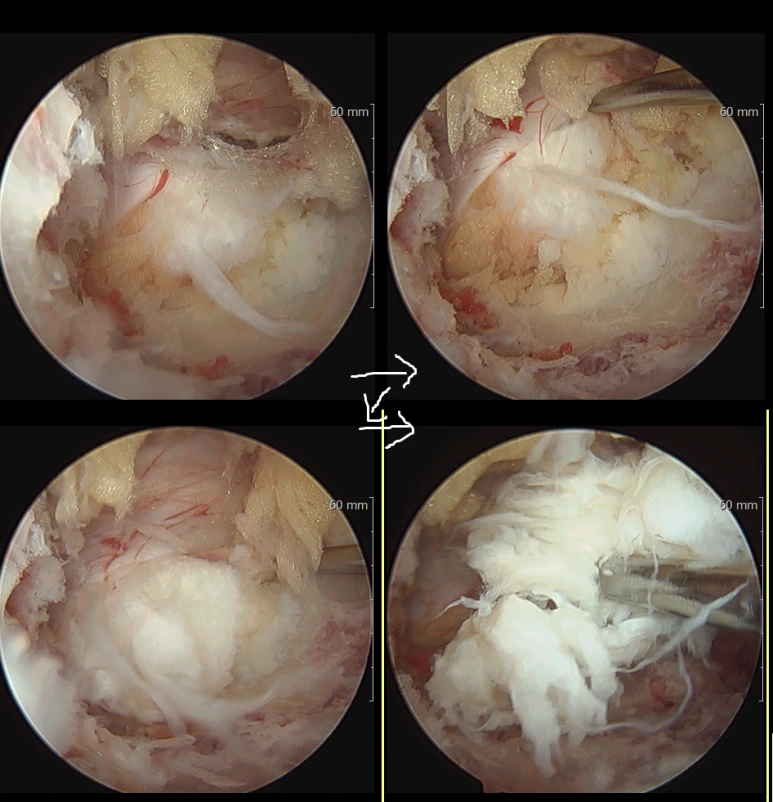

내시경 보면서 터져나온 디스크를 제거하는 모습. 반짝거리는 금색 물질은 지방, 디스크 위 혈관이 덮인 밝은 핑크색 막은 신경과 뇌척수액을 담고있는 경막입니다. 사진 상방이 medial(내측, 가운데 쪽), 좌방이 cranial(머리 쪽). 30도 내시경으로 찍은 사진. (환자분 동의 받았습니다)

내시경으로 보면서 수술 깔끔하게 진행되었고, 디스크는 거의 다 제거되었습니다.

디스크가 up migrated 되어있어서 뼈를 많이 갈아낼 수도 있다고 생각되었는데 (hemilaminectomy 가능성) 지난번처럼 30도 내시경 덕분에 손상부위 거의 없이 안전하게 수술 진행됐습니다.